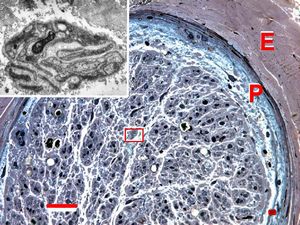

Demyelinized nerve with bands of Büngner (square, inset) . P- perineurium, | E - epineurium. (Human, sural nerve.) Scale 0.2 mm.

n. suralis - hypertrophic demyelinizing neuropathytoluidine-blue-stained semithin section